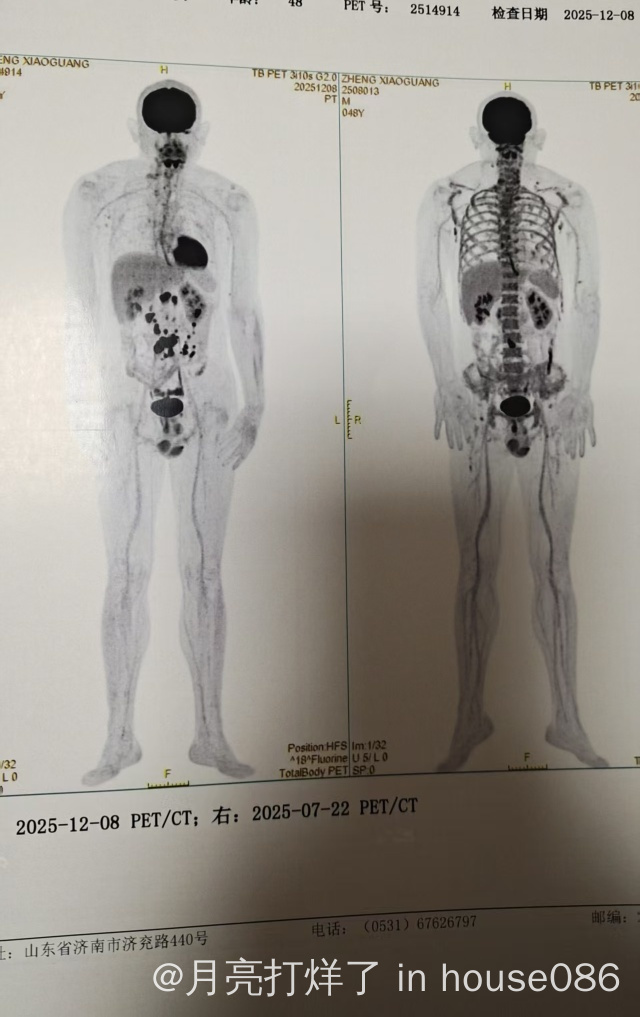

我爸爸今年四月底查出滤泡型淋巴瘤2级四期其中最大的腹部包块大概7cm,进行了八次化疗,前两次G-CHOP效果不明显,后续换成依托泊苷96小时不间断,四疗结束pet腹部已经变成1.2cm,10月结疗后未做pet现在过两个月来复查pet-ct比中期增多了腹部变成1.9,现在不知道该怎么治疗了,不知道这边有什么好的建议吗,谢谢!

图1-4是第一次检查的pet 、病理报告和骨髓穿刺

图5、6是四疗后pet

图7-9是这次检查的pet